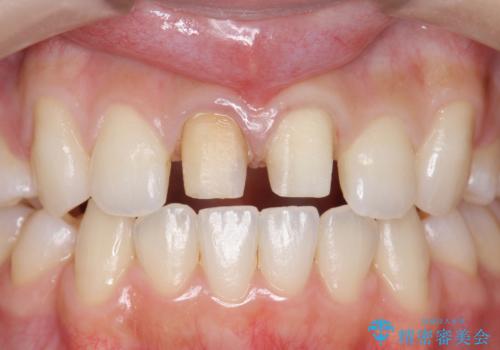

前歯の変色 セラミックで ホワイトニングも併用

- 神経のない前歯が変色していたため、矯正治療後にセラミックで修復しました。

セラミックの前に、全体をオフィスホワイトニング(エクセレント)して周りの歯を白くして色をなじませました。

右の前歯は当院で根管治療をやり直しています。(根管治療はDr.大元が担当しました。)